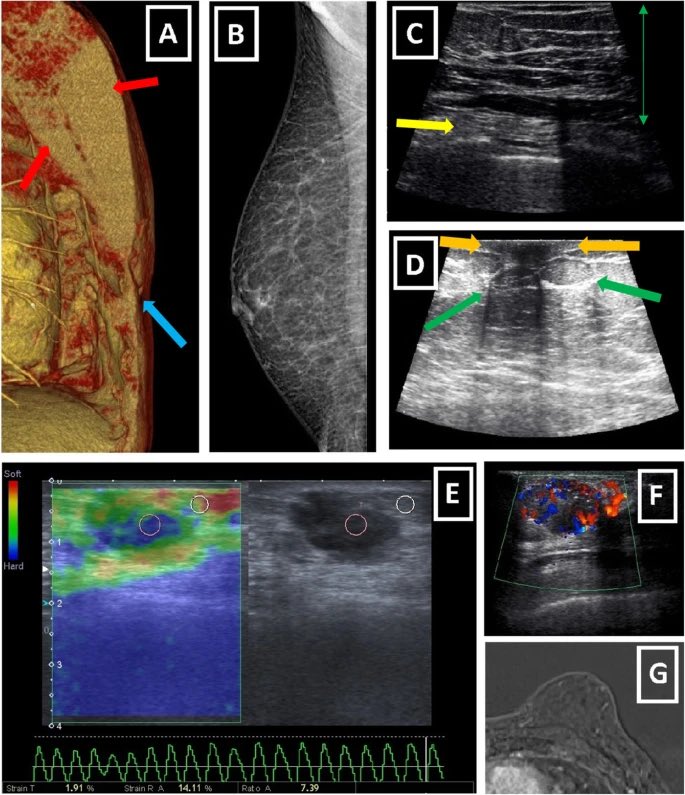

7️⃣وعادة بتم طلب فحص

١-الأشعه فوق الصوتية، لمعرفة نوع وصفات التورم او التغير

٢- احيانا يحتاج لعمل تصوير الثدي الشعاعي أو الماموغرام

في حال تبين ان الضخامة ليست نتيجة تثدي نحتاج لعمل

٣- خزعة، يتم فيها ادخال ابرة للثدي وشفط عدد من الخلايا للفحص في مختبر بالميكروسكوب